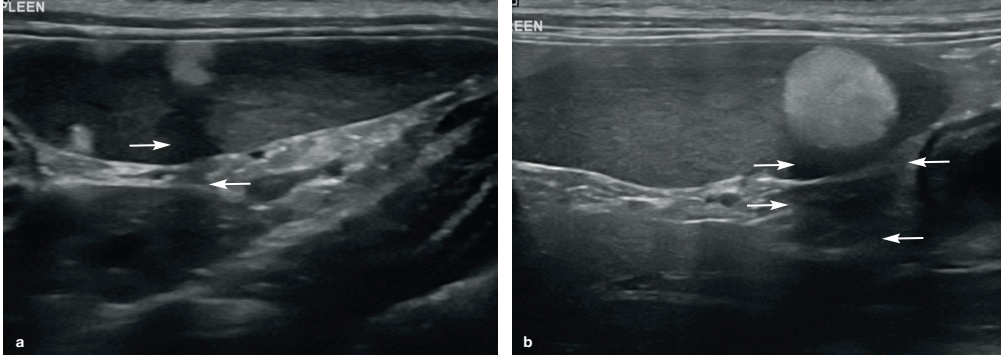

② Myelolipoma(골수지방종) 와 다른 고에코성 병소들: 나이든 고양이나 치타를 포함한 다른 고양잇과에서는 잘 구분되는 고에코성의 결절을 실질 내 혹은 비장 경계부위에서 볼 수 있습니다. 이는 myelolipoma로 알려진 지방의 결절을 말하며, 우연히 발견됩니다. 이들은 단독 혹은 여러 개의 결절로 구성되어 있으며 때로는 희미한 음향 음영(acoustic shadowing)을 나타내기도 합니다(그림 9).